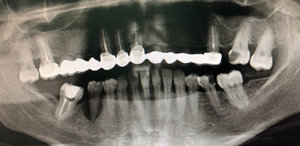

4 месяца назад мне сделали вкладку на предпоследний зуб нижней челюсти, при этом рядом стоящий ближний зуб удалили, т.к. было нагноение на десне. Я не сделала коронку на один зуб, т.к. хотела закрыть просвет и от недостающего зуба. Но и стачивать ближний зуб (здоровый) мне не хотелось. На дорогой имплант средств не нашлось. Сейчас зуб со вкладкой стал побаливать и на десне снова появилось нагноение. Из-за чего это произошло и что мне теперь делать? Явилось ли моё промедление результатом нагноения или это могло произойти и под коронкой?

Добрый день . Конечно это произошло бы и под коронкой, так что не мучайте себя. Дело в самих каналах, вернее в плохо пролеченных каналах, что повлекло обострение воспалительного процесса.

Одним словом вам необходимо к врачу и как можно раньше и постараться спасти зуб.